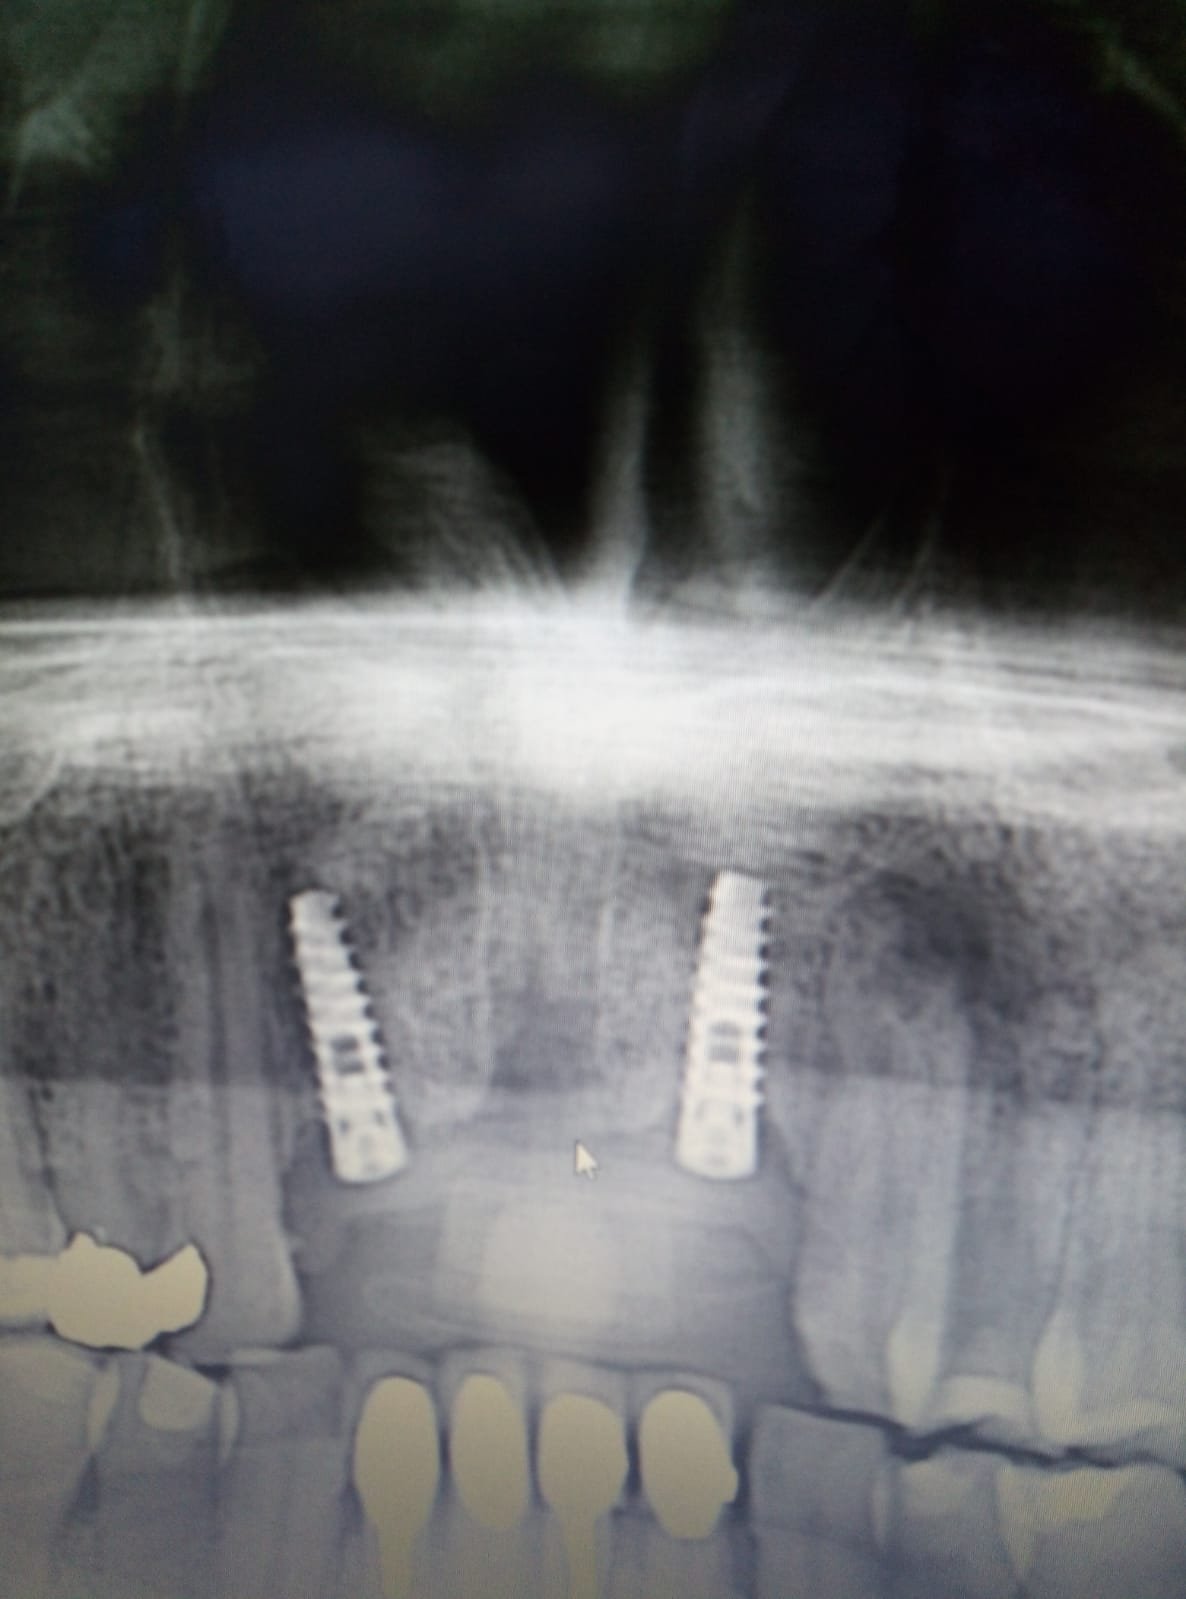

implantes en el sector anterior. que son?

hola chicos, me ha venido este paciente con los implantes en el sector anterior y no sabemos que son. el hombre no lleva protesis y el no se acuerda en [...]